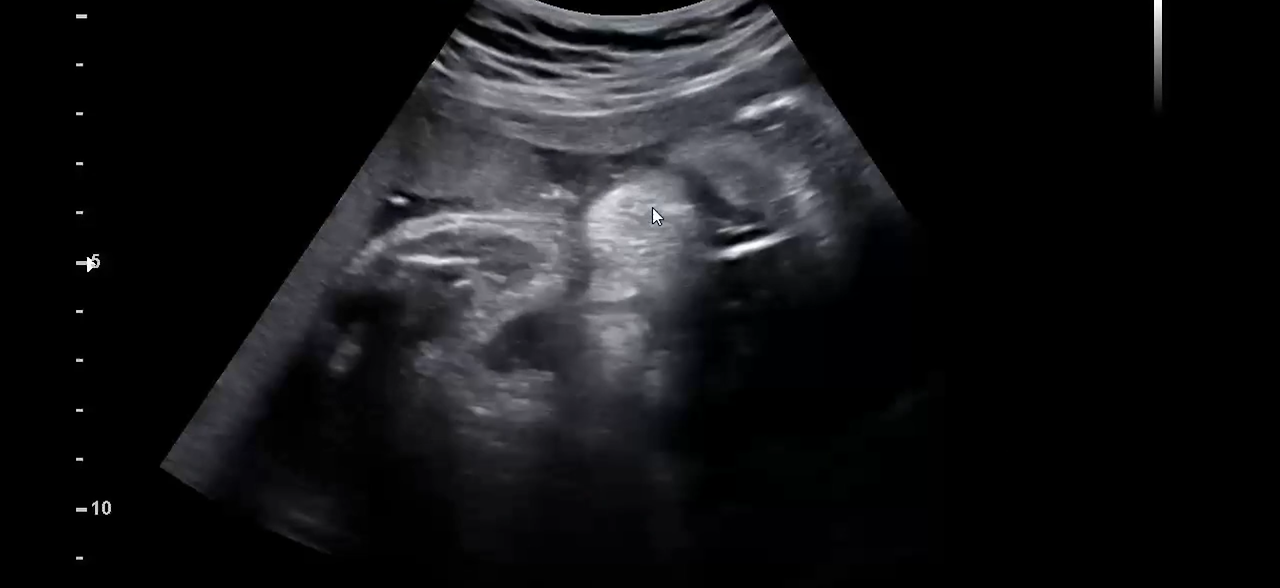

31주 명절을 보내고 온 임산부

오랜만에 당뇨식이 아닌 식단을 해서 그런지 뱃속의 아가는 품은 중에 제일 격럴한 태동을 보여주었고. 사촌언니 애기들까지 모여 왁자지껄한 명절다운 분위기를 냈다. 생가보다 당 수치도 수치인이었고 명절스트레스 라고 할만한 것들도 하나도 없어서 왜 걱정을 했는가 생각을 했다.

그렇게 출산 전 빅 이벤트라고 할 수 있었던 명절을 보내고 이제 차분하게 출산을 준비하기만 하면되는 주차가 되고 있다. 더이상의 이벤트 없이 순산 할 수 있기를 빌며.